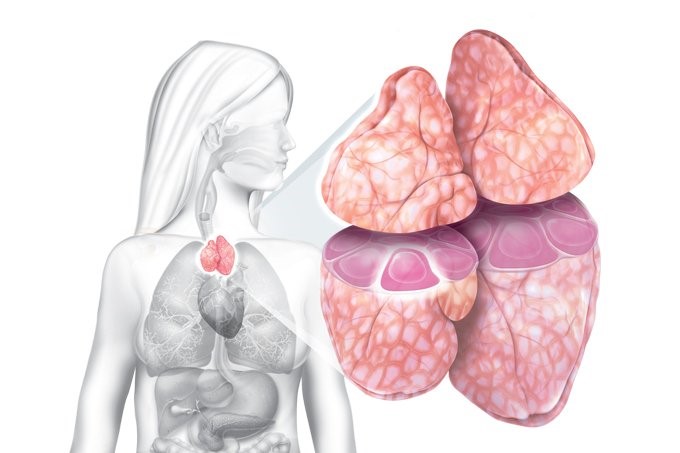

TIMO

É no timo que vamos encontrar células epiteliais corticais com citoplasmas abundante, estas células liberam um tipo de interleucina, a IL-7 que irá possibilitar a maturação das células T.

Na etapa inicial da maturação, ocorre a proliferação celular dos timócitos na região mais externa do córtex, bem como o rearranjo dos genes do T cells receptor (TCR), além da expressão das moléculas de CD3, TCR, CD4 e CD8 na superfície celular.

E a medida que os timócitos maturam estes migram do córtex para a medula tímica (2).

Podemos definir que o estroma tímico consiste de células epiteliais, macrófagos e células dendríticas derivadas da medula óssea além de fibroblastos e moléculas da matriz extracelular.

A interação dos timócitos com as células do microambiente tímico é fundamental para a proliferação, a diferenciação celular, a expressão de moléculas de superfície, como o CD4 e CD8, e a criação do repertório de receptores de LT (2-4).

Durante todo o processo de desenvolvimento dos timócitos, cerca de 95% deles morre por um processo natural de apoptose. Tal fato acontece devido a alguns fatores, mas de forma principal, devido aos arranjos mal sucedidos das cadeias de TCR e aos processos de seleção positiva e negativa, o que leva a somente 3% a 5% de timócitos que se tornarão Linfócitos T maduros (4).

Imagem e localização do Timo.